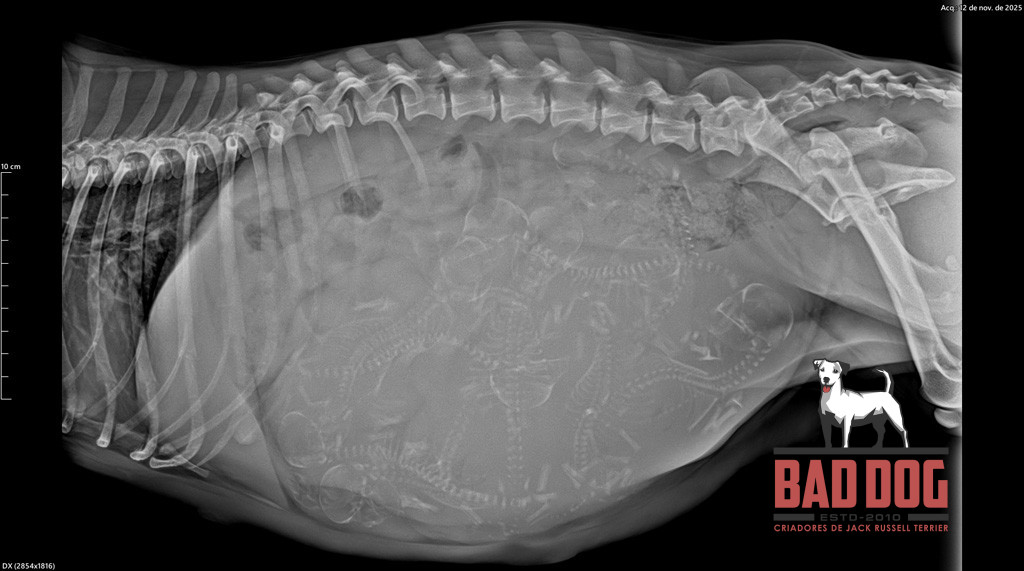

Ninhada PHI 2

Eco Oliva PHI2_oliva-rx2

3 of 39